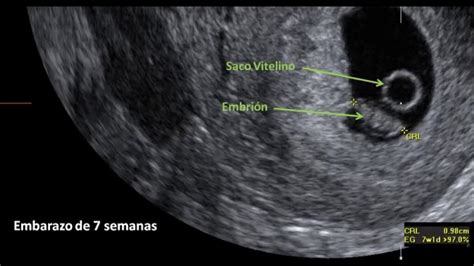

3. Ecografía Transvaginal:

Esta es la herramienta diagnóstica principal. Permite visualizar el útero y los ovarios, buscando la presencia del saco gestacional. Si se confirma un embarazo pero no se visualiza dentro del útero, se sospecha fuertemente un embarazo ectópico. La ecografía también puede detectar signos sugestivos como un "anillo tubárico", una masa extrauterina, líquido libre en la cavidad pélvica o, en casos más avanzados, un saco gestacional fuera del útero con o sin embrión y latido cardíaco.